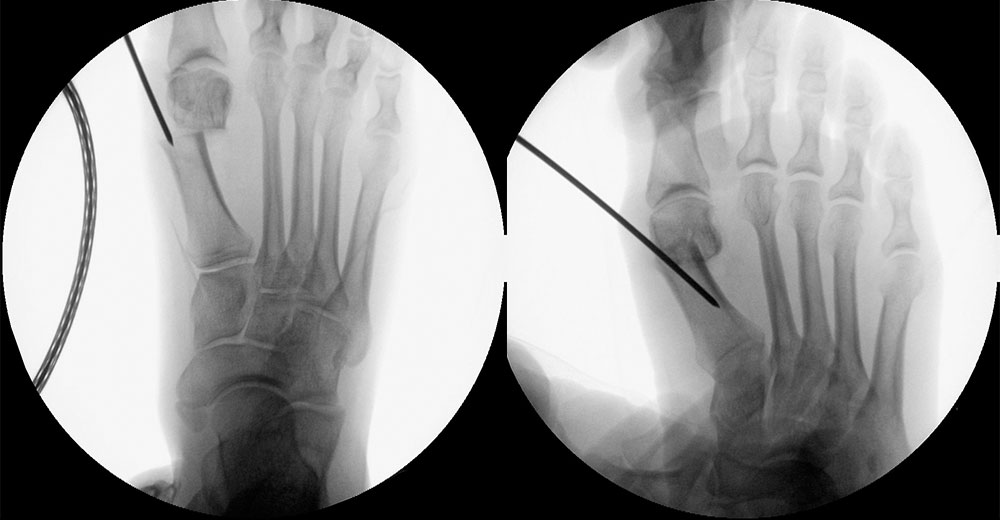

Abbildung 1

• Korrekturpotential größer als beim offenen Chevron, da die Gelenkkapsel als stabilisierendes Element erhalten bleibt und über eine trikortikale Osteosynthese mit zwei kanülierten Schrauben eine Verschiebung bis ca. 80% des Metatarsaledurchmessers möglich ist (Abb. 1).